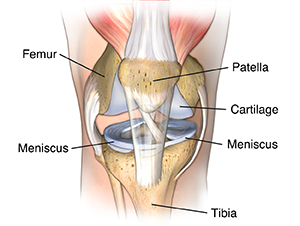

There are three bones in the knee. These are the femur, tibia, and patella. The ends of those bones are covered with cartilage. This is a smooth material that cushions the bone and allows the joint to move easily without pain. The cartilage acts as a shock absorber. Between the bones of the knees are two crescent-shaped disks of connective tissue, called menisci. These also act as shock absorbers to cushion the lower part of the leg from the weight of the rest of the body.